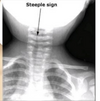

Appearance: The wrist and hand are weak (claw-hand) and lack a grasp reflex. If sympathetic nerves are involved, unilateral miosis (Horner syndrome) may result.

A

Dx: Clavicular Fracture.

ipsilateral Moro

2

Croup: CXR

“steeple sign”